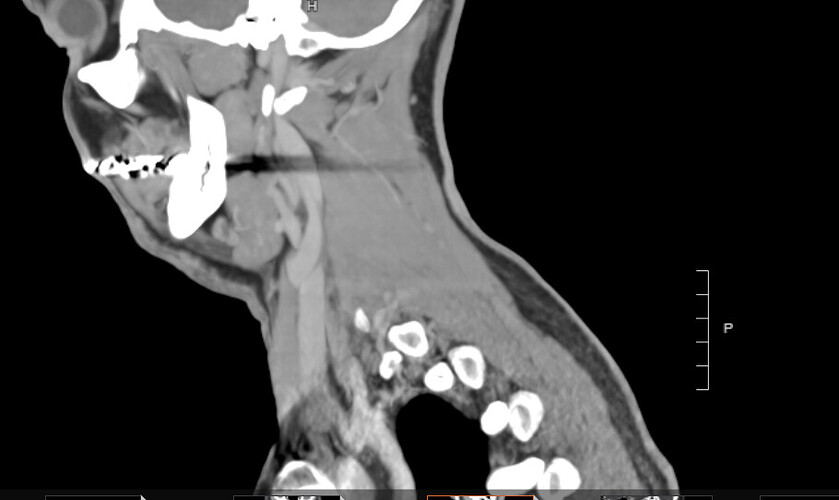

I got back some of my images from my CT scans. Still not 100 percent sure what ones I need to look at, so would love to input. Here’s one which seems to show left compression and I can’t tell if the right is a little compressed.

Just above the level of C1, both styloid make contact with your IJVs. The compression is worse on your left side, which is also your non-dominant (smaller) IJV.

At the level of C1, both IJVs are compressed, with compression much worse on your left. On your left side, both your styloid and C1 are contributing. On your right side, only C1 is contributing to the right IJV compression. Important to note that when the IJV is compressed at C1, so too may the vagus nerve(s), as they run between the IJVs and C1. Vagus compression could present as HR & BP fluctuations, anxious states, and stomach issues.

Further down, you have a long pocket of calcified stylohyoid ligament on both side. On your left side, the calcification comes very close to your left ECA. It is likely that the calcification does sometimes come in contact/compress the ECA with swallowing or certain head positions. ECA compression/irritation can radiate pain to the ear and down the length of the artery into the chest.